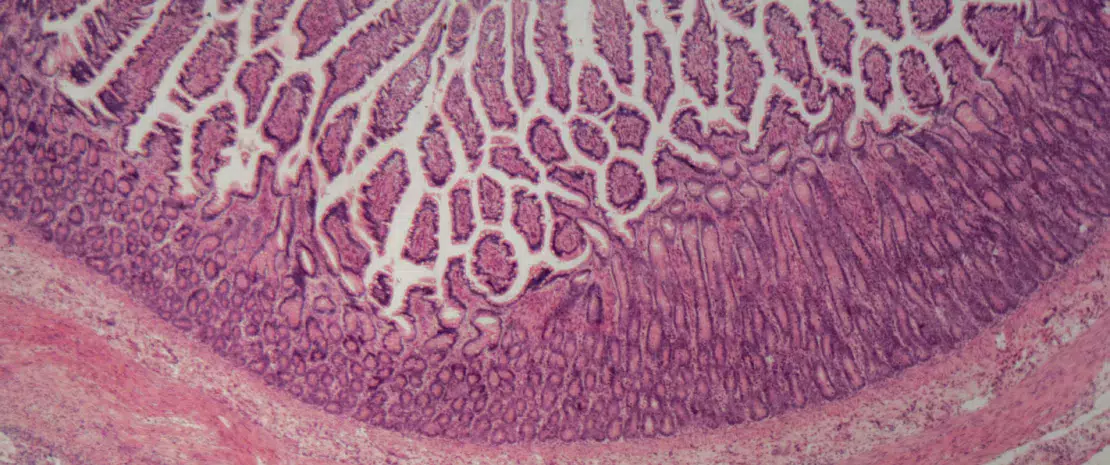

Rôle de l’épithélium intestinal et de la réponse immunitaire innée

La dysbiose observée dans les MICI pourrait être liée à une altération de l’épithélium intestinal, devenu incapable de jouer son rôle de barrière, ainsi qu’à un dérèglement de la réponse immunitaire innée locale favorisant l’inflammation. Explications et zoom sur les peptides antimicrobiens suspectés d’y contribuer.

L’altération de la barrière intestinale observée chez les patients souffrant de MICI pourrait expliquer la physiopathologie de la dysbiose : non seulement cette frontière mécanique serait altérée, mais aussi sa première ligne de défense immunitaire. Outre son rôle dans l’absorption d’ions, d’eau et d’autres nutriments, la barrière intestinale sert de rempart et empêche l’entrée de bactéries dans la lumière intestinale.

Or sa perméabilité augmente lors des phases aiguës de maladie de Crohn (MC), ce qui favorise la translocation de bactéries à travers la muqueuse et l’inflammation locale5.

Le rôle de la barrière intestinale

Possiblement en cause : l’altération des jonctions serrées des cadhérines de l’épithélium intestinal (des glycoprotéines jouant un rôle-clé dans l’adhérence intercellulaire) ; l’implication de certains facteurs de transcription11 liés à la régénération épithéliale. Les autres mécanismes évoqués concernent le mucus intestinal, dont l’épaisseur maintient les bactéries pathogènes à distance et qui s’avère considérablement amoindrie chez les patients MICI. Le phénomène s’expliquerait par l’altération des cellules caliciformes, productrices de mucus, dont la perturbation induit le développement de colites sur des modèles murins ; il s’expliquerait également chez les malades MC par le dysfonctionnement des cellules de Paneth, situées au fond des cryptes de l’intestin grêle, réputées participer à l’homéostasie et au rôle de défense de la muqueuse intestinale via la sécrétion d’antimicrobiens5,11.